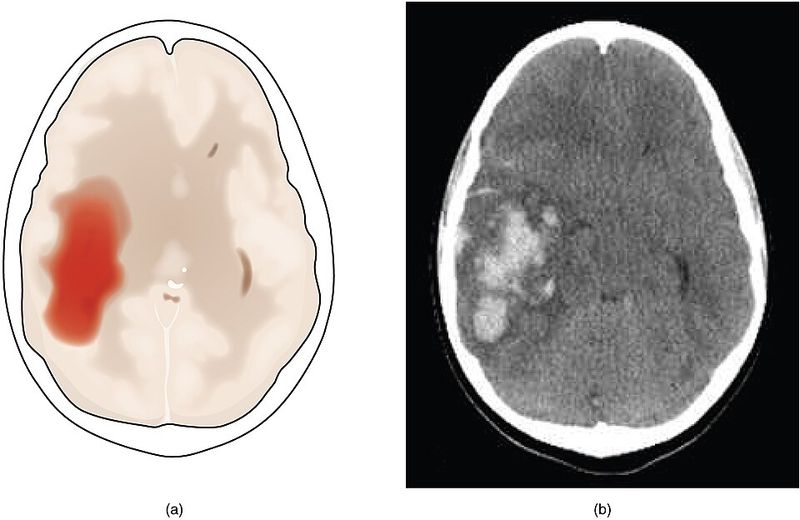

Hemorrhagic strokes are less common than ischemic strokes, but when they happen, they’re often much more serious. They involve bleeding in the brain, which can cause rapid and severe damage.

Survival rates are lower, and recovery is often harder.

That’s why it’s so encouraging that the strongest association in this study was with hemorrhagic stroke. A 25% lower risk for the most dangerous type is a quiet but powerful win.

The mechanisms likely involve blood pressure control and vessel integrity. Chronic high blood pressure weakens blood vessel walls, making them more prone to rupture.

A diet rich in potassium, healthy fats, and antioxidants helps keep pressure in check and vessels strong. While ischemic strokes get more attention because they’re more common, reducing hemorrhagic stroke risk is equally, if not more, important.